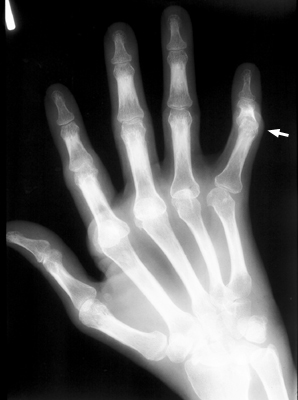

Boutonniere Deformity

Rheumatoid arthritis

Among the many osseous abnormalities that may be seen in Rheumatoid Arthritis, the boutonniere deformity is the culmination of multiple abnormalities in the hand. Specifically, the deformity arises from hyperextension of the distal interphalangeal joint, while the proximal interphalangeal joint is flexed.